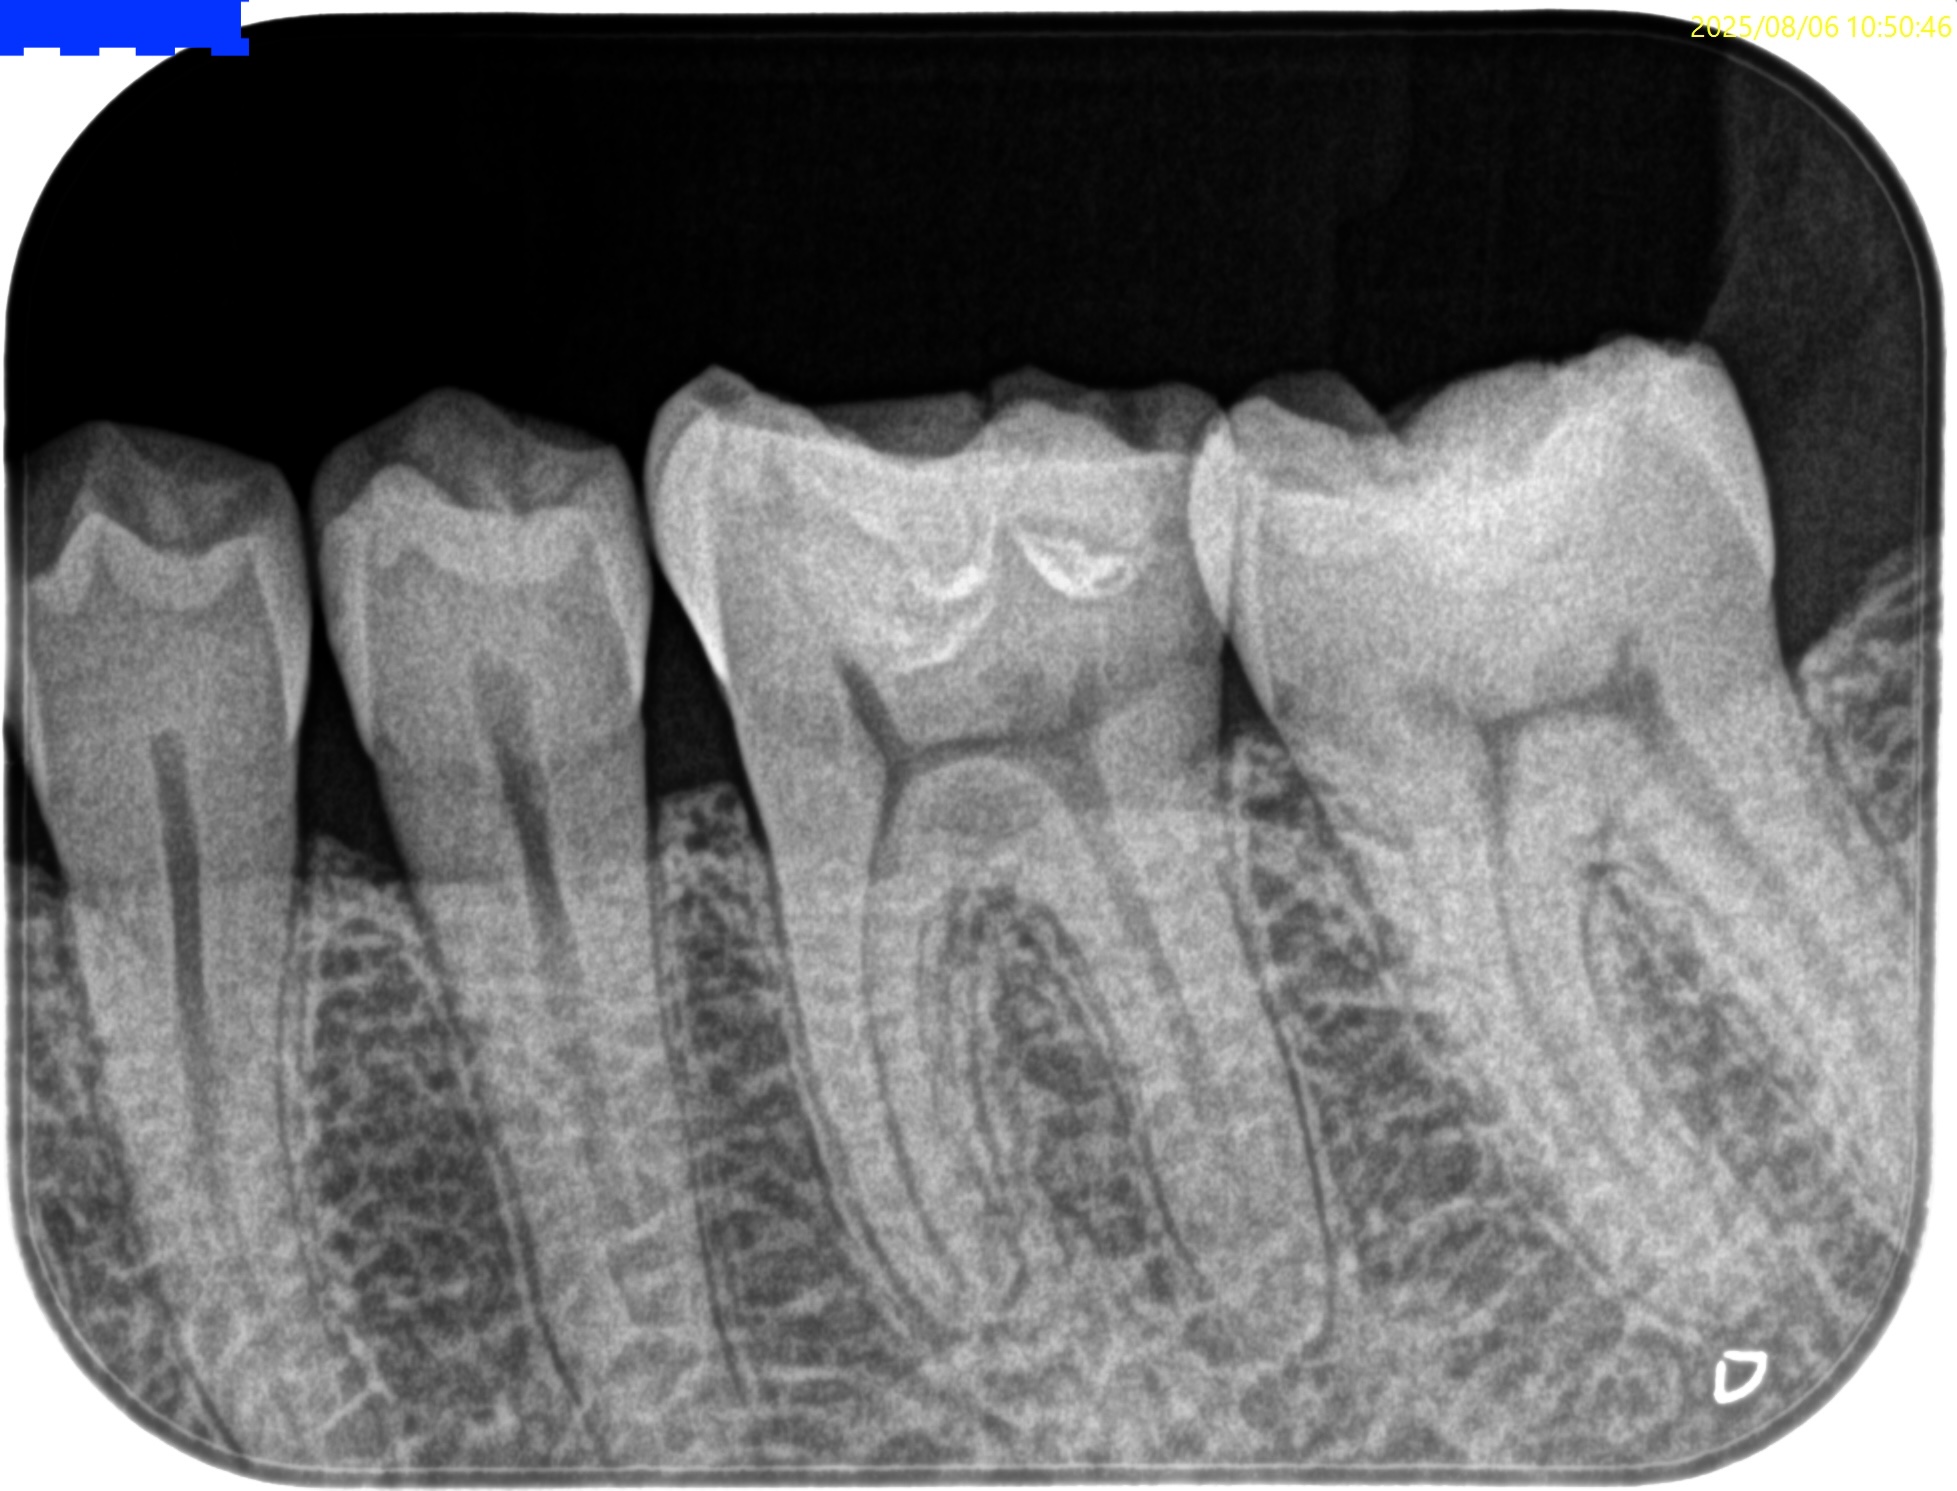

参考ケースは以下だ。

Dにはほぼ歯髄に修復物が覆いかかっている。

これは、

Asymptomatic irreversible pulpitisの可能性が高いだろう。